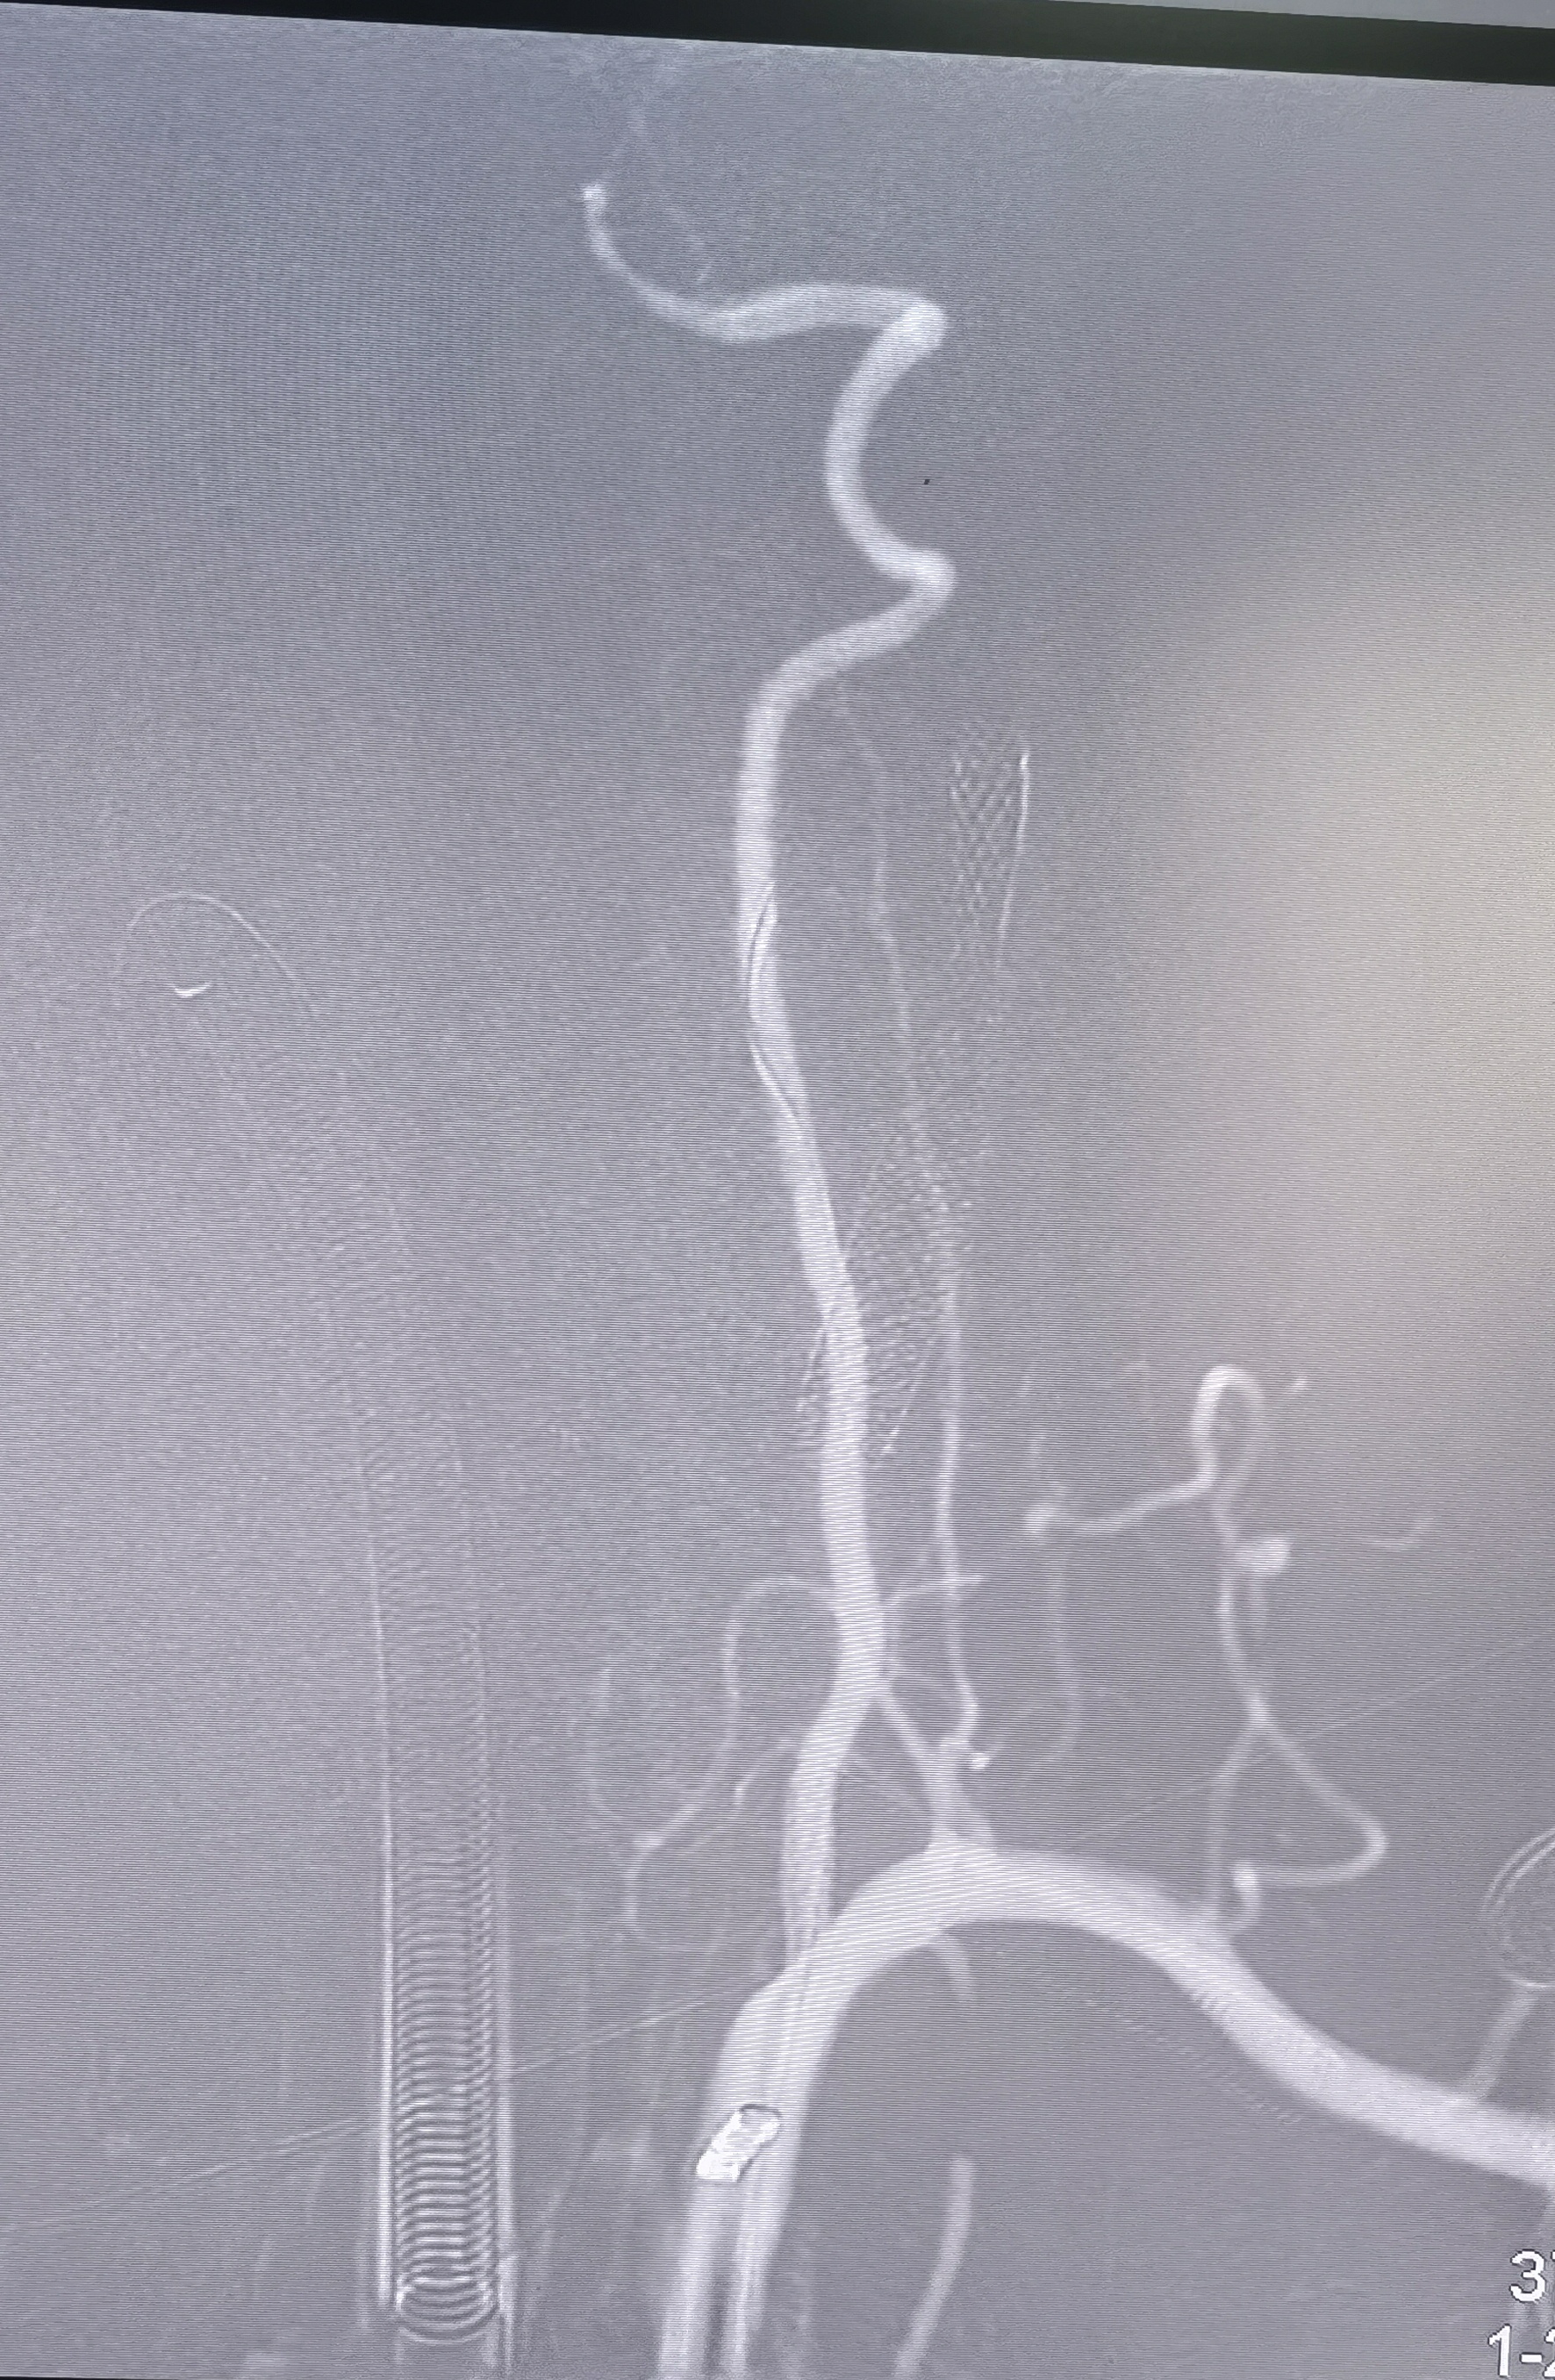

支架置入

支架置入后造影侧位